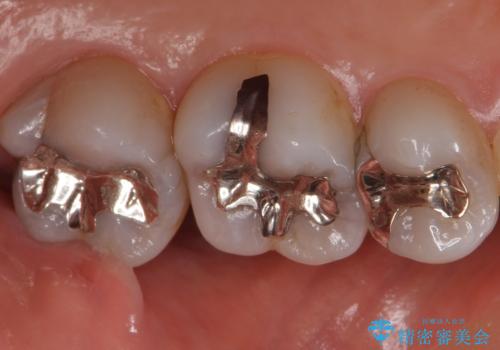

- 銀歯を白くしたいとのことで来院されました。

特に大きな虫歯もなかったため、周りの歯を残しつつセラミックインレーでの修復処置をしていきます。

大きな虫歯さえなければ、銀歯のやり替えは詰め物の周りの歯を保存しつつ修復することができます。